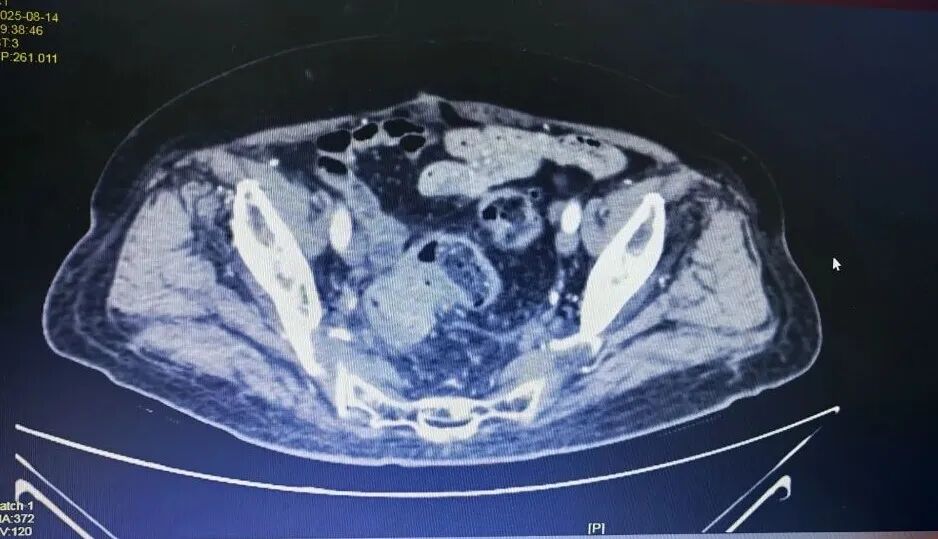

CT下病灶

尤其是结肠癌合并脓肿及不完全性梗阻,胆囊结石伴胆囊炎,随时可能引发感染加重、穿孔、脓毒症等危象;而患者同时存在的动脉硬化、髂动脉血栓,更如同“定时炸弹”,术中术后随时可能因血栓性疾病导致危及生命;加上肾功能不全、痛风等,使得麻醉和手术风险增加。